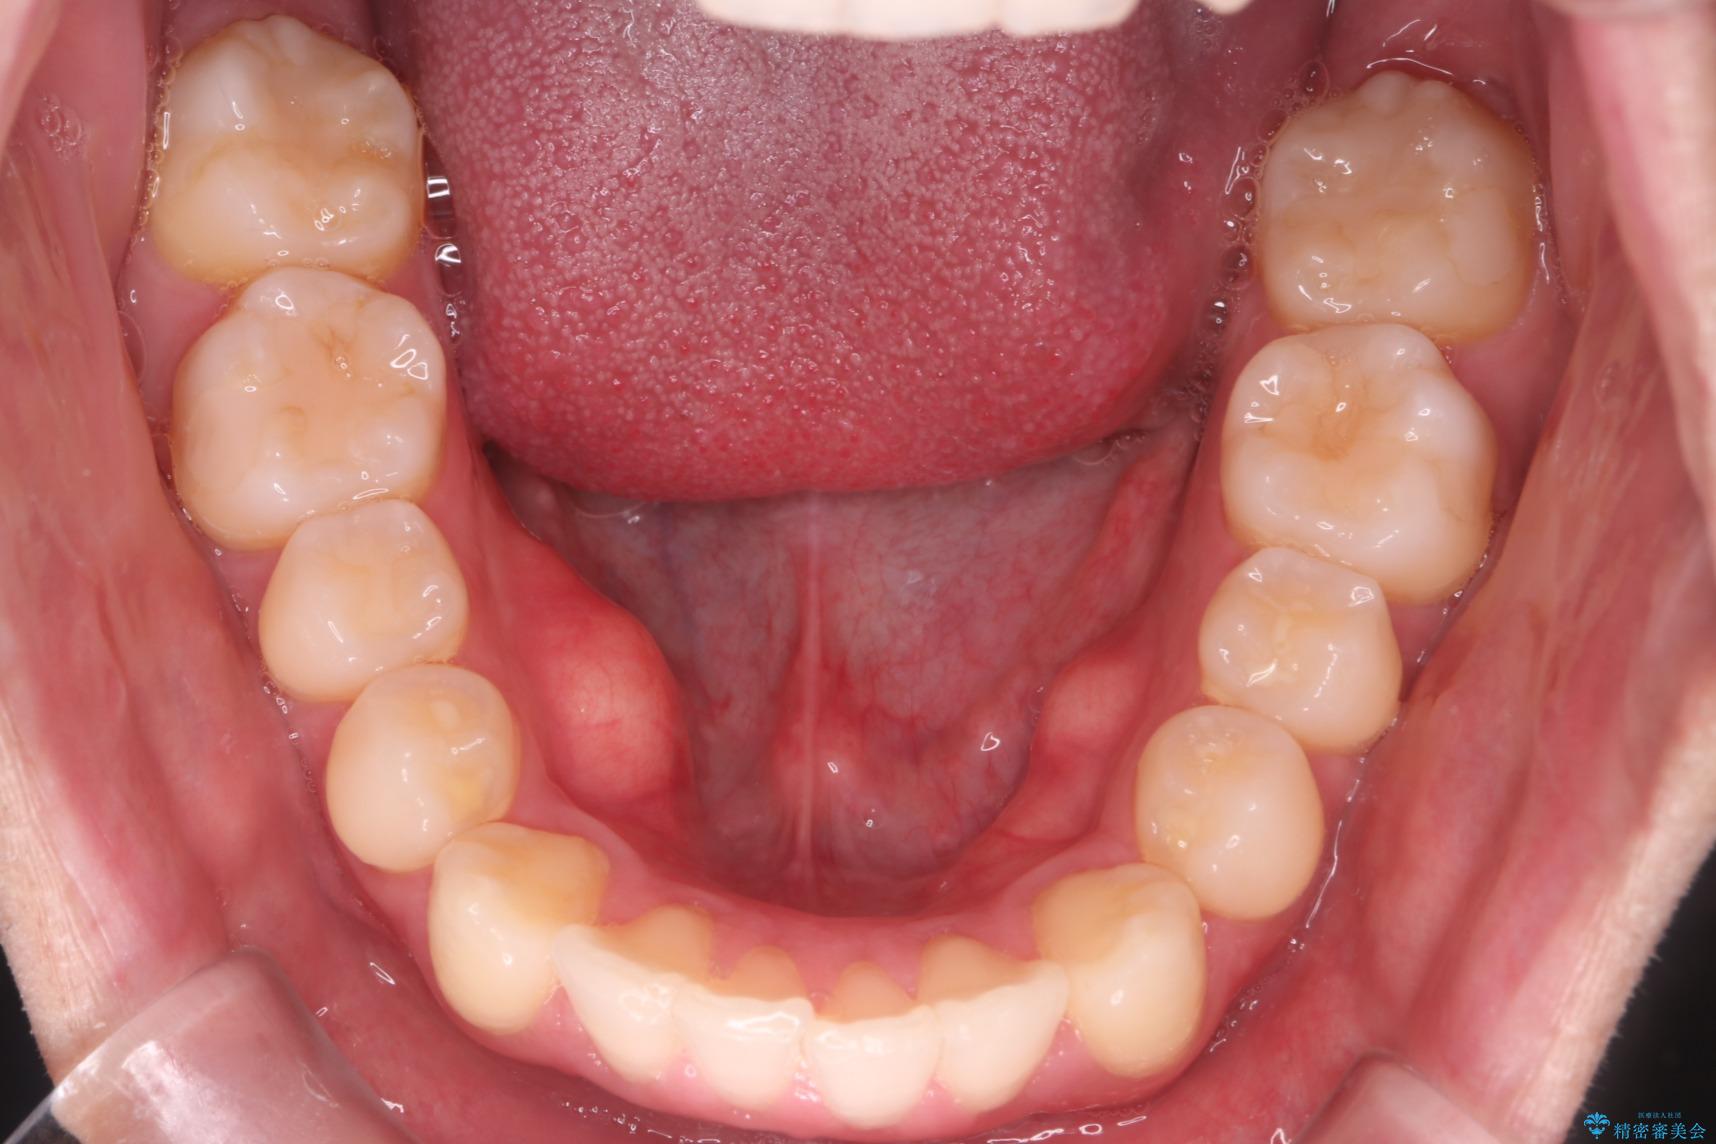

治療計画

インビザラインでの治療を希望されました。

IPR(歯と歯の間を削る処置)を行うことで、前歯の位置とがたつき整える治療計画を立てました。